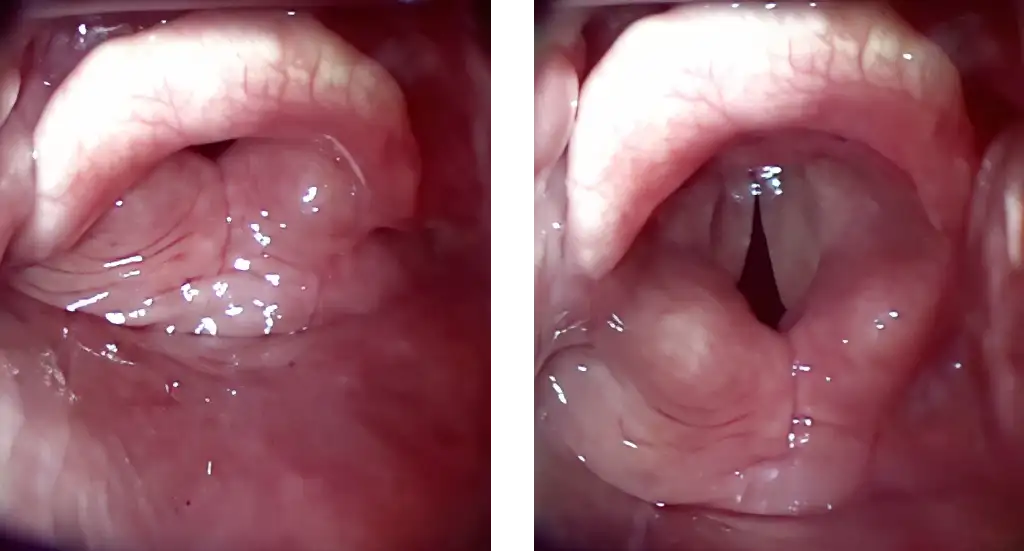

If vocal cords are not seen it is very likely that Airtraq has been inserted TOO DEEP, if so perform the following maneuver:

A gent lift of the Airtraq causes the glottis to open and drops the interarytenoid notch below the middle of the image (optimal position for successful ETT insertion)